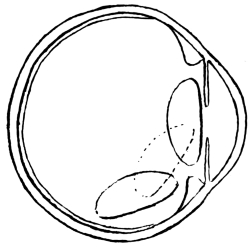

Fig. 3.—Depression.

Fig. 4.—Reclination.

The above two figures illustrate the path taken by the cataract during the operation. (Mackenzie.)

The introduction of reclination, as opposed to depression, by Willburg in a Nuremberg thesis, dated 1785, gave a fresh lease of life to couching in its dying struggle with the operation which was destined to supersede it. England, France, Sweden, Germany, and other countries, joined vigorously in the discussion, and amongst the powerful advocates of couching were ranked Percival Pott and William Hay of London, Cusson of Montpellier, and Scarpa of Pavia, whilst Benjamin Bell practised both couching and extraction. The admirable treatise by James Ware on cataract (1812) was all but a death-blow for Celsus’s operation. The newer procedure was then well in the ascendant, and only needed time to completely strangle its rival. Notwithstanding this, it was left to Mackenzie, so late as 1854 (fourth edition), to give the most complete and interesting description of couching to be found in literature. He distinguishes sharply between the operations8 of depression and reclination. In depression, the lens is pushed directly below the level of the pupil, being made to follow the curvature of the eye, to sweep over the corpus ciliare, until it comes to rest on the lower curve of the eyeball, with its anterior surface directed forward and downward (Fig. 3). In reclination, the lens is made to turn over towards the bottom of the vitreous chamber in such a way that what was formerly its anterior surface now comes to look upward, and what was its upper edge is turned to the rear. The whole lens is swung backward as if on a hinge, composed of the lower fibres of its suspensory ligament, which still remain unbroken (Fig. 4).

Fig. 5.

He divides the operation of couching into four stages, in only the last of which reclination differs from depression. These are: (1) the pushing of a special needle (Fig. 5) through the coats of the eye at a distance of 1/6 inch behind the temporal edge of the cornea, and to a depth of 1/5 inch; (2) the laceration of the posterior capsule of the lens by vertical movements of the point of the needle, to prepare an aperture for the passage of the lens; (3) the passing of the needle into the anterior chamber around the edge of the lens, and the laceration of the anterior capsule by vertical strokes; (4a) to depress the lens, the point of the needle is carried over its upper edge, and the handle is9 raised a little above the horizontal, thereby correspondingly lowering the point, which forces the cataract downward out of sight behind the pupil: the needle is then withdrawn by rotation; (4b) to effect reclination, the needle-point is raised not more than 1/10 inch above the transverse diameter of the lens: its concave surface is pressed against the cataract, which is reclined by moving the handle of the instrument upward and forward, thereby causing its point to pass downward and backward. The cataract is thus made to fall over into the vitreous humour, and is then pressed downward, backward, and a little outward. Mackenzie adds many interesting details as to the modifications of the operation, according to the variety of the cataract to be dealt with, and as to the after-treatment and complications met with.